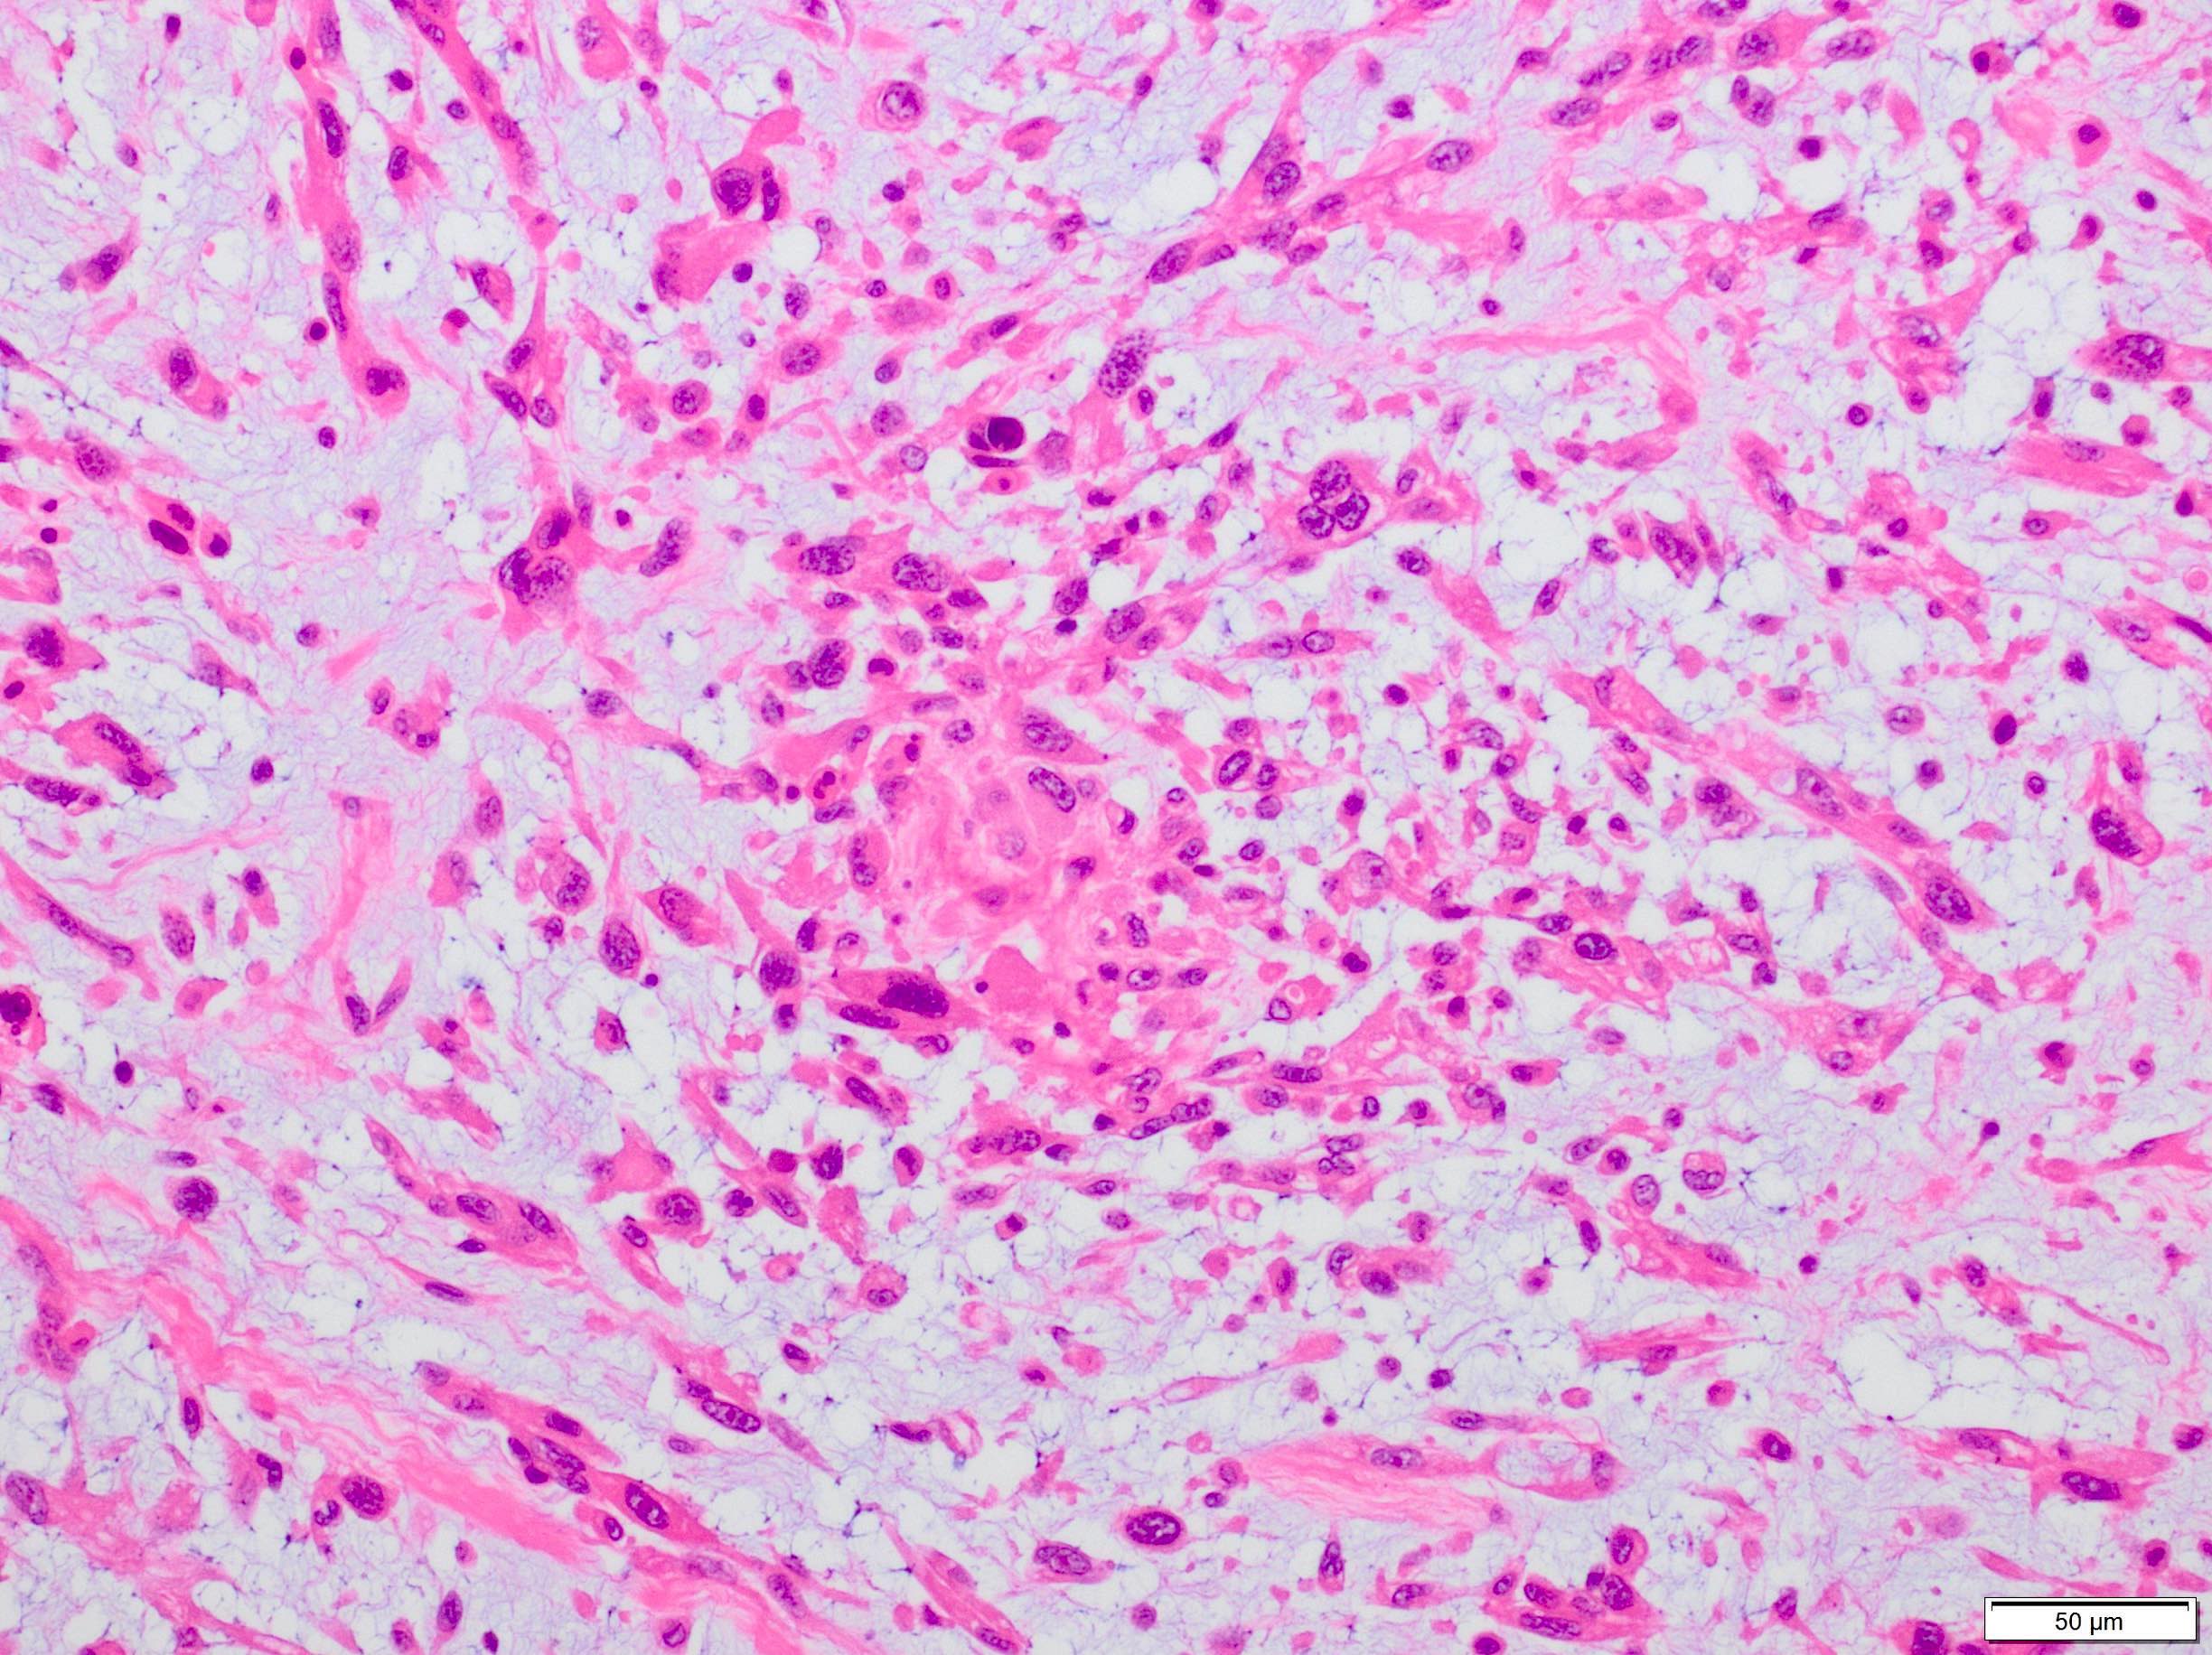

Microscopic (histologic) description

- Sheets of large, atypical and frequently multinucleated polygonal, spindled or rhabdoid eosinophilic cells (Am J Surg Pathol 2009;33:1850)

- Cross striations are seldom detected

Microscopic (histologic) images